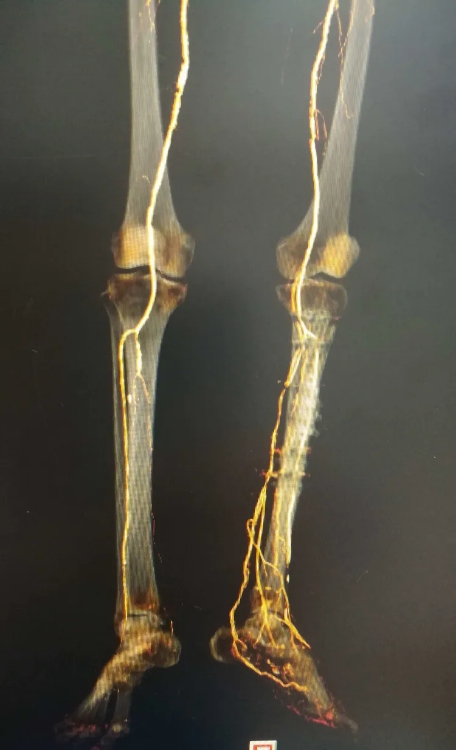

骨搬运手术后,产生大量的新生血管网

搬运后血管网密集